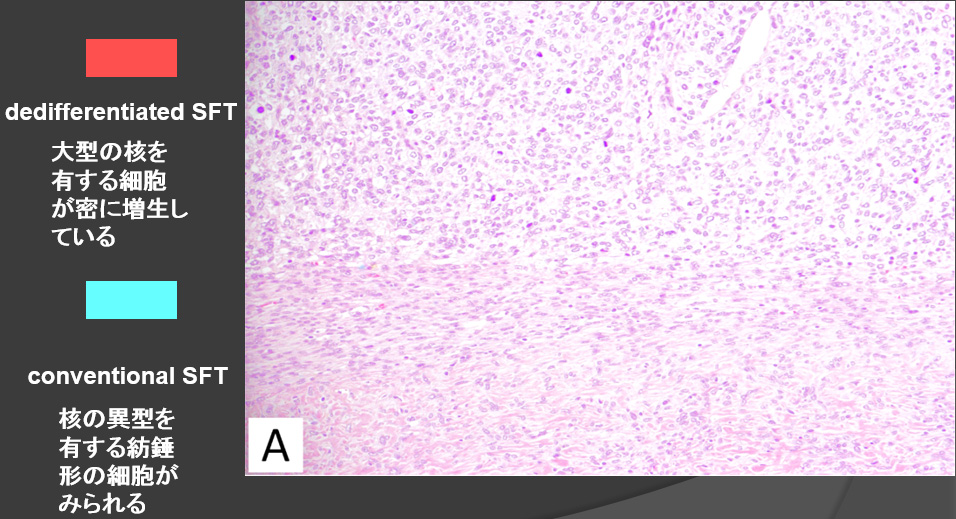

- 【病理所見】

Dedifferentiated solitary fibrous tumor (SFT) in the pelvis

- 骨盤部に発生したdedifferentiated SFTの1症例を経験した。

頻度は稀であるが、SFTが脱分化して肉腫化し、他の肉腫との鑑別が困難となることがある。